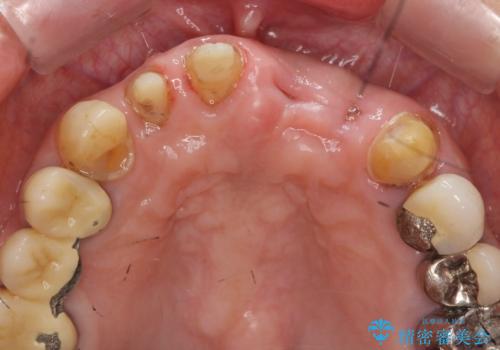

X線検査・視診より強くぶつけた前歯は折れてしまい、抜歯が必要な状況です。

元々の噛み合わせが深く(ディープバイト)、転んで顎を強打したことで上顎前歯2本が根元から折れてしまい抜歯をしなければいけない状況となってしまいました。